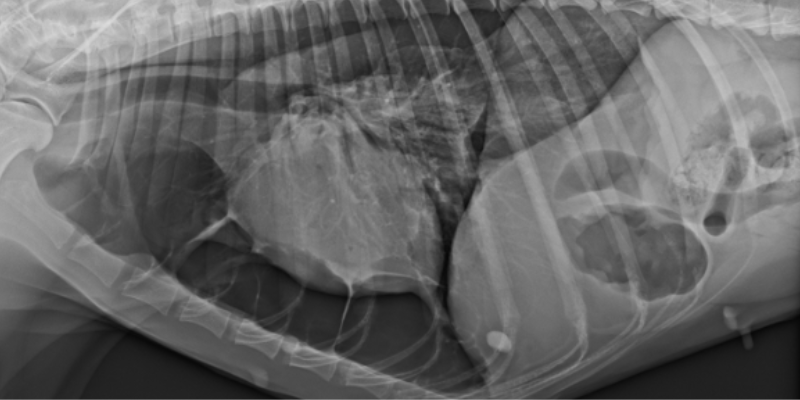

An x-ray of the collapsed lung of Beck, an Irish Setter, at Animal Emergency & Referral Center of Minnesota.

Our first step was imaging. Dr. Saveraid, one of our board-certified veterinary radiologists, performed a chest CT scan on Beck that confirmed a left-sided collapsed lung. A CT scan often doesn’t reveal the cause of a collapsed lung – but it did help us determine that Beck didn’t have an obvious mass.